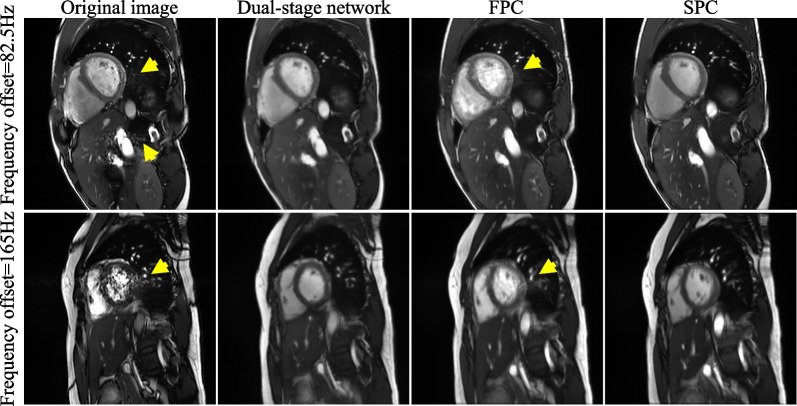

Figures 3 and 4 show exemplary suppressions of the banding and flow artifacts by the dual-stage network, FPC, and SPC at two frequencies. All three methods well suppressed the banding artifacts relative to the original images (Fig. 3). However, only the dual-stage network and SPC well suppressed the flow artifacts, whereas FPC did not (Fig. 4). The qualitative analysis (Fig. 5) shows that both the network and FPC achieved banding artifact scores of 4.30 ± 0.40 and 4.60 ± 0.31, respectively, higher than that of the original cine (2.53 ± 0.42). However, for flow artifacts, the dual-stage network achieved higher scores than both the original cine (4.57 ± 0.23 vs 3.00 ± 0.35, P = 0.002) and FPC (3.40 ± 0.38, P = 0.002). Furthermore, the overall quality of the dual-stage network was significantly higher than the original cine (4.33 ± 0.22 vs 3.00 ± 0.47, P = 0.002) and FPC (3.60 ± 0.38, P = 0.002), likely due to the better suppression of flow artifacts. ICCs of the 3 readers were 0.87 (95% CI [0.64, 0.94]) for banding artifacts, 0.60 (95% CI [0.28, 0.80]) for flow artifacts, and 0.58 (95% CI [0.16, 0.80]) for overall image quality.

Fig. 3.

A representative example of banding artifact suppression by the proposed network, FPC, and SPC at two different frequencies. Banding artifacts appeared in the heart, abdomen, and subcutaneous fat regions (yellow arrows). All three methods suppressed these banding artifacts. FPC, full-range phase cycling; SPC, short-range phase cycling

Fig. 4.

A representative example of flow artifact suppression by the proposed network, FPC, and SPC at two different frequencies. Flow artifacts appeared in the heart and abdomen regions (yellow arrows). Both the dual-stage network and SPC well reduced flow artifacts. On the other hand, FPC still resulted in considerable flow artifacts in the heart region. FPC, full-range phase cycling; SPC, short-range phase cycling